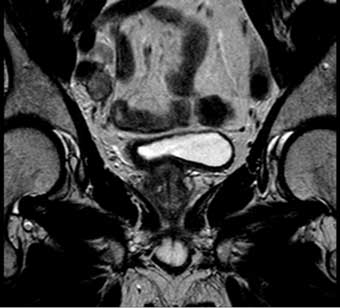

Hình 2. Hình ảnh MRI xung T2 cắt ngang cho thấy một khối u bên phải,đồng thời cho thấy u chưa lan ra ngoài bàng quang.

Hình ảnh T2 nên được thu thập hoặc tái tạo trong ba mặt phẳng. Hình ảnh T2 cho phép đánh giá khối u nguyên phát và thành bàng quang (Hình 2) và vượt trội hơn so với hình ảnh T1 trong việc đánh giá sự xâm lấn vào các cơ quan lân cận như tuyến tiền liệt hoặc tử cung. Cũng như phim cắt ngang (axial), một khối u bàng quang ở thành bên hoặc ở vòm được đánh giá tốt nhất trên phim cắt đứng ngang (coronal) và một khối u phía trước ở mặt phẳng đứng dọc (sagittal).